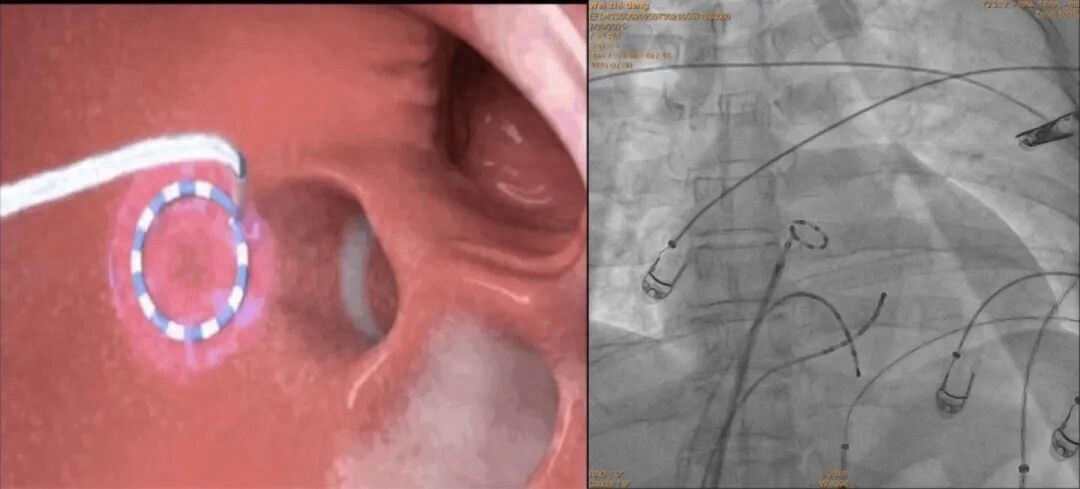

经石闯主任团队全面评估,决定为患者实施最新的脉冲电场消融术(PFA)。手术过程顺利,术后患者恢复良好,复查心功能、肝功能等指标均恢复正常,困扰多年的症状得以解除。

石闯主任指出:脉冲消融术(PFA)是一种革命性的非热能消融技术。它通过释放超短高压电脉冲,精准“击破”引发房颤的异常心肌细胞,而对周围的食管、神经等重要组织影响极小。其核心优势在于:

1、高度精准:像“精准导弹”,只靶向问题细胞,安全性高。

2、非热能量:避免传统热灼伤或冷冻损伤,组织损伤更小。

3、高效快捷:单次放电仅毫秒级,手术时间显著缩短。

4、效果持久:临床研究显示其复发率低,能为患者带来长期稳定疗效。